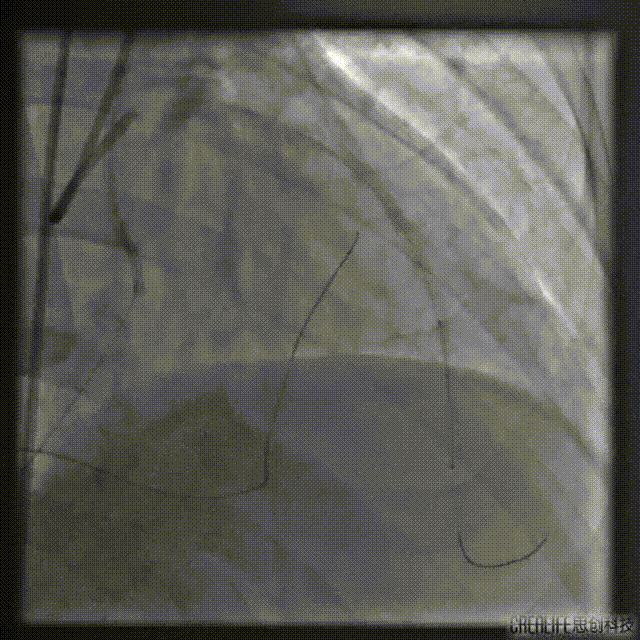

考虑间隔支侧枝纤细且存在显著成角迂曲,选择1.5F HighTrack微导管作为逆向微导管,支撑SION导丝进入侧枝。

SION导丝受限于严重迂曲无法通过,遂更换为SUOH 03导丝,通过侧枝走行至LAD闭塞处后反向前送至LAD远段,HighTrack微导管通过侧枝跟进至分叉处。

逆向导丝更换为P200后仍不能突破CTO远端纤维帽至LAD近段,遂调整前向导丝Kissing逆向导丝进入间隔支,送入1.5mm球囊扩张LAD至间隔支。

试图用SUOH03 逆向Knuckle至LAD近段未成功,遂将SUOH03导丝推送至LAD远段。

再次尝试正向开通

通过双腔微导管送入P200导丝Kissing逆向导丝,最终在肝位Kissing进入LAD远段。